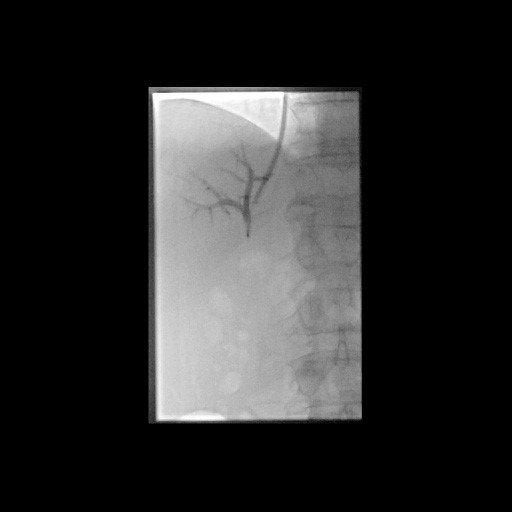

Erfolgreiche Implantation eines transjugulären intrahepatischen portosystemischen Shunts (TIPSS) bei Leberzirrhose und refraktärem Aszites. Darstellung der Lebervenen

(Bild 2 von 4)

Erfolgreiche Implantation eines transjugulären intrahepatischen portosystemischen Shunts (TIPSS) bei Leberzirrhose und refraktärem Aszites. Transhepatische Punktion der Pfortader unter sonographischer Kontrolle

(Bild 3 von 4)